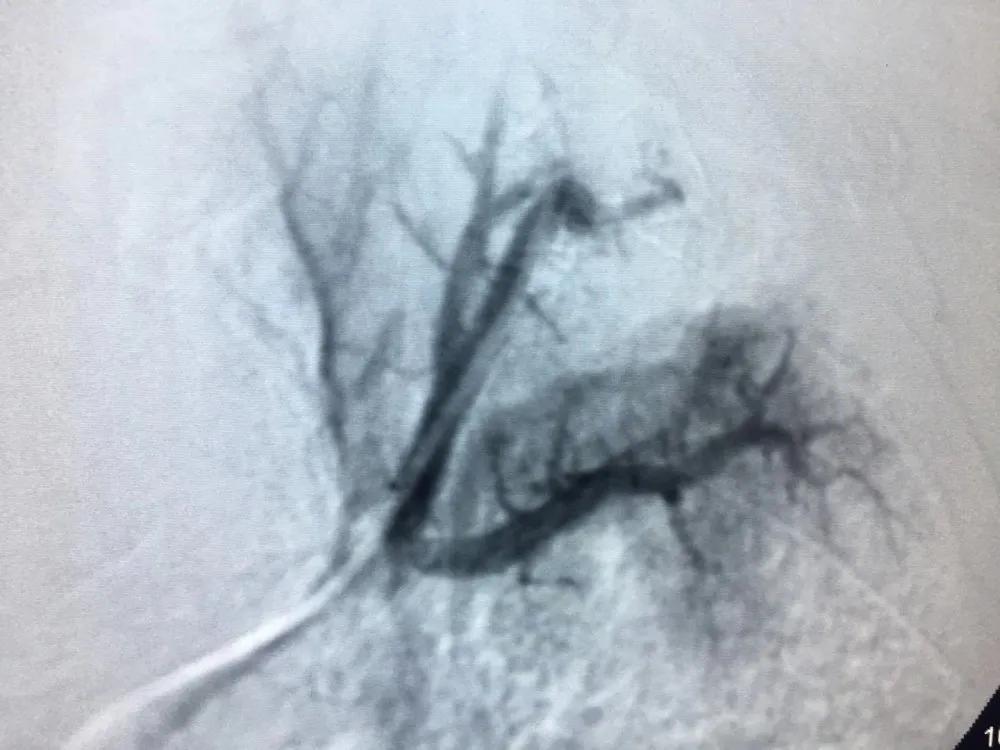

手術進行了2個小時,術中造影可見患者左、右支氣管動脈、隔動脈、肋間動脈等多支血管異常增粗、迂曲、遠端可見出血病灶;左上肺動脈分支末端見假性動脈瘤,是出血的“罪犯血管”,即行支氣管動脈栓塞和肺動脈假性動脈瘤栓塞術。術后患者咯血停止,無并發(fā)癥及不良反應發(fā)生,手術獲得了滿意的效果。